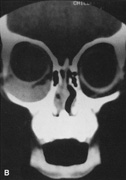

Fig. 25. A,B. Coronal (A) and axial (B) CT scans demonstrating well-encapsulated mass posteriorly in the superonasal orbit. An excellent alternative to transcranial orbitotomy for this lesion is an anterior approach via a vertical-lid splitting incision.

Procedure